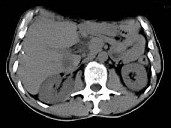

- 单项选择题根据所提供的图像,最可能的诊断是 ( )

A、转移癌

B、肝细胞癌

C、肝脓肿

D、肝血管瘤

E、以上都不是